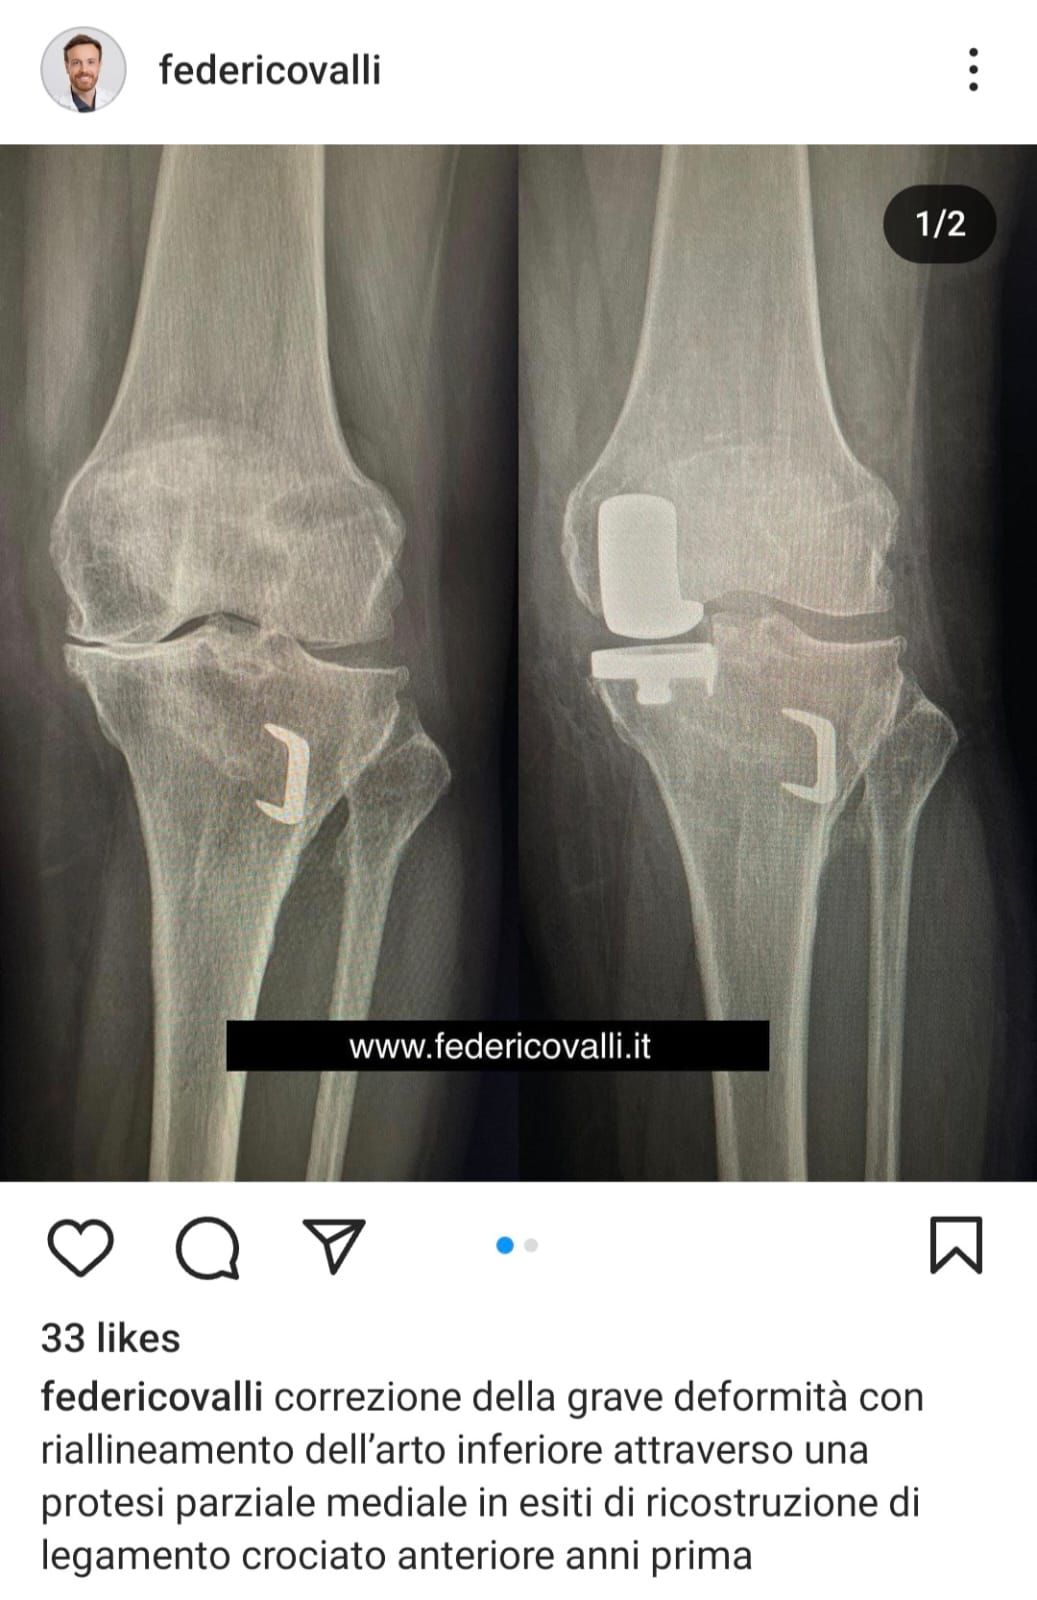

Oggi primo controllo dopo intervento di protesi monocompartimentale ginocchio destro ....tutto benissimo Grazie Dot Valli